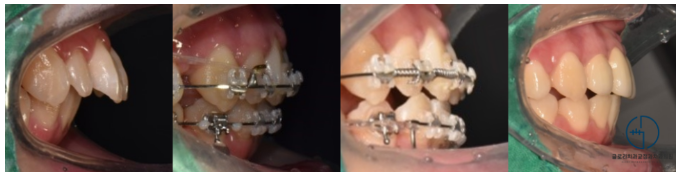

앞서 계획했던 대로 상악 소구치 발치를 통해

후방이동을 할 수 있게끔 배열공간을 확보했습니다.

잇몸을 보면 미니스크류의 모습을 확인할 수 있는데요.

『왜 미니스크류를 사용하여

치료를 도왔을까요?』

미니스크류를 사용하여 전치를 후방이동 시키면

구치의 이동 없이 완전한 전치의 후방이동을 얻을 수 있기 때문이죠.

이후 코일 스프링 및 고무줄의 도움을 받아

좀 더 긴밀한 조정을 통해

안정적인 배열이 될 수 있도록 유도했습니다.

배열은 어느정도 자리가 잡혔으나

상악 앞니의 형태 및 크기가 눈에 띄네요.